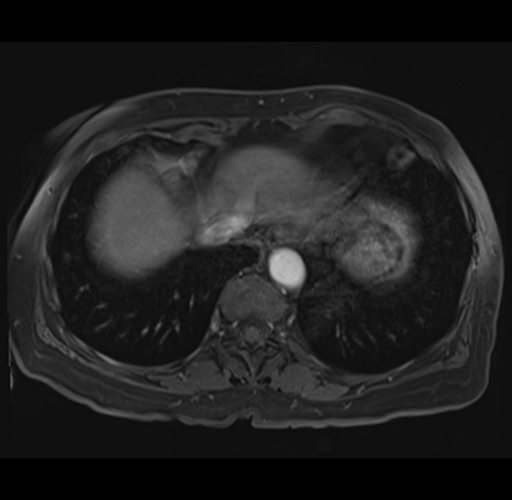

MRI T1